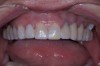

Figure 30  Final restorations.

Figure 30